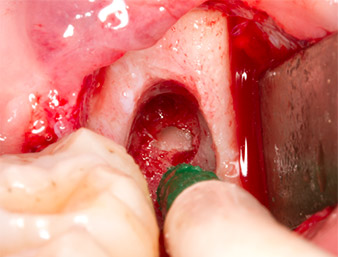

Using an instrument for periodontal debridement (Piezomed P1), the periodontal ligament space of the radix relicta was then widened minimally (Fig. 8).

The same activated instrument was inserted into the root canal and loosened the fragment as a result of its micro-oscillating vibrations (Fig. 9, 10).

Piezomed P1

Fig. 9: The Piezomed P1 instrument is recommended by the manufacturer primarily for periodontal debridement but is also suitable for surgical purposes. Here it is placed in the root canal after minimal widening of the periodontal ligament space.

Fig. 10: Due to its slender shape, the instrument can penetrate the root canal and remove the root remnant by means of micro-oscillation (vibration).